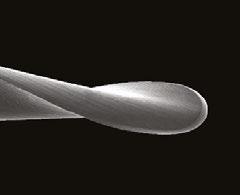

With these engineered solutions that minimize breakage, the only remaining concern about using rotary negotiation as FFL is the possibility of rotary file tips blocking, ledging, or perforating the often tortuous apical regions of canals. This is why file tips on these rotary negotiators are fully radiused. This extremely passive tip geometry not only prevents ledging and perforation, but also actually causes these rotary files to kind of “bump” around impediments that would absolutely be engaged by an unbent hand file. While blockage is always a concern when advancing a file into apical regions of vital canals during negotiation procedures, it turns out that the way hand files function when used in a watch-wind, push-pull manner is actually the cause of most apical blockage.

Figure 2: PlanB’s 15-.03 miniKUT EZP Rotary Negotiation File. Note the square cross section and the aggressive rake angles of the four flutes, providing torsional strength with cutting efficiency (middle). The completely passive “duckbill” file tip geometry eliminates the chance of ledging curved canals during rotary negotiation as FFL (right). The side view shows flute angles that are consistent from tip to shank, preventing file threading and tip breakage (left)